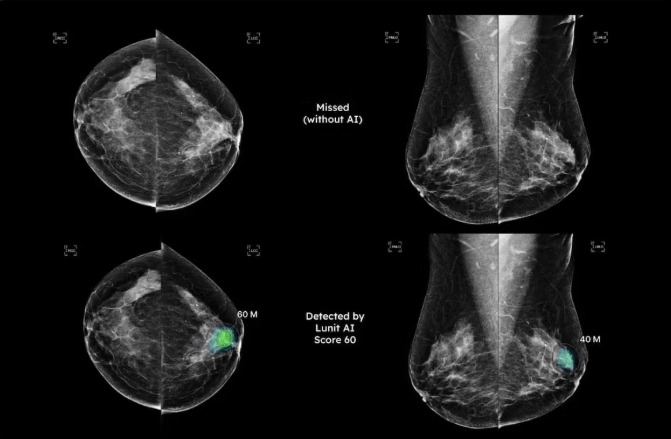

一项涉及6.7万名女性、超过13.5万次筛查性乳腺X光摄影的研究显示,人工智能软件Lunit Insight MMG的检查风险评分(ExRS)能有效预测后续筛查中的乳腺癌检测。该研究结果近期在欧洲放射学大会(ECR)上公布,平均随访时间为777天。

研究发现,在451名患上乳腺癌的女性中,基线平均ExRS为15.4,后续筛查ExRS为73.9;而未患乳腺癌的女性基线平均ExRS为6.7,后续筛查平均ExRS为6.4。意大利威尼托大区特雷维索卫生局放射科主任Clauda Maria Weiss医学博士及其同事指出:“AI衍生的ExRS能够在基线区分女性患乳腺癌风险的不同水平,并且这种能力在所有乳腺密度类别中保持一致。”

在患乳腺癌的女性中,乳腺不密实(BI-RADS类别A和B)的女性基线平均ExRS为13.8,后续筛查ExRS为73.7;乳腺密实(BI-RADS类别C和D)的女性基线平均ExRS为17.6,后续筛查ExRS为74.1。Weiss和同事补充道:“结果表明,ExRS也可用于筛查中基于风险的分层。”